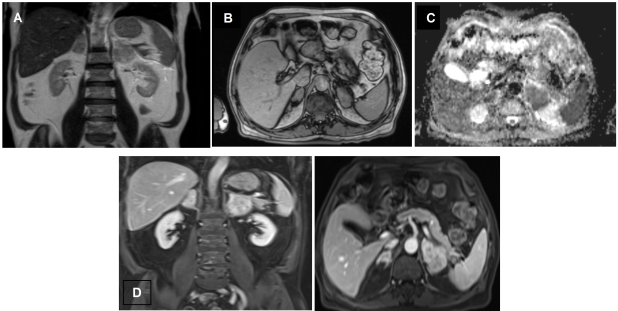

Hombre de 69 años, con antecedentes de diabetes mellitus tipo 2, EPOC, hipertensión arterial y dislipidemia, quien presentó cuadro clínico de un mes de evolución consistente en pérdida de 7 kg de peso, disminución de la clase funcional, dolor abdominal, episodios eméticos y deposiciones diarreicas sin moco ni sangre. Se documentó hiponatremia, hipercalcemia, insuficiencia adrenal primaria (cortisol 5,8 µg/dL, ACTH 646,4 pg/mL) y anemia normocítica normocrómica. Se realizó TC tóracoabdominal simple, evidenciando masas adrenales bilaterales sólidas, de densidad homogénea con atenuación de 29 UH, sin calcificaciones (fig. 1). Para mejor caracterización de las lesiones adrenales se realizó RM abdómino-pélvica, mostrando en las secuencias T2 una señal alta, en las T1 supresión grasa pre-contraste con una señal baja y homogénea. Con el medio de contraste se observó realce progresivo, con áreas de restricción a la difusión en las secuencias de difusión y mapa ADC. No se comprobó enfermedad metastásica ni invasión de estructuras adyacentes (fig. 2).